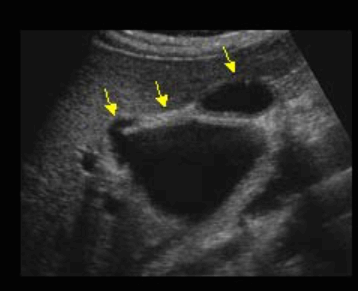

parallel channel sign & shotgun sign 미리찌 증후군 (Mirizzi's syndrom)

미리찌 증후군 (Mirizzi's syndrom) Mirizzi's syndrom 은 담낭경부, Hartmann's pouch 혹은 담낭관의 결석에 의해 총 간관(CHD)이 폐쇄되는 질환이다. 총 간관(CHD)이 협착되면서 상부담관은 확장되고 하부담관의 직경은 정상으로 나타난다. 증상은 폐쇄성 황달, 복부통증, 발열 등이 나타난다. 급성담낭염이 있으면서 담관폐쇄를 동반할 경우 의심해 볼 수 있다. 담낭절제술 후에 남아있는 담낭관의 결석이 총 간관(CHD)을 직접 누르거나 염증성 협착을 유발하기도 한다.

US finding

- 담낭관 또는 담낭 경부에 결석이 확인된다.

- 총간관(CHD) 또는 담낭관(cystic duct)의 확장소견이 보인다.

- 간내외 담관의 확장이 관찰된다.